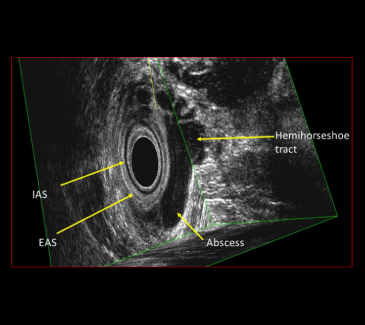

Endoanal Ultrasound

- Provides a detailed 3D multiplanar reconstruction of the anal canal

- Accurate mapping of complex anal fistulas and anal abscesses for precise surgical planning

- Delineates anatomy of anal sphincter

- Rapid, simple and well- tolerated